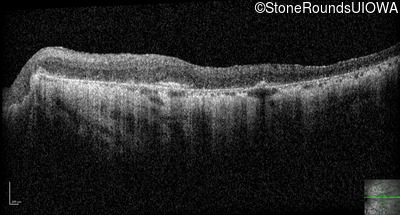

Optical Coherence Tomography - Left - 20/200 -2

Exemplar / OCT Stack